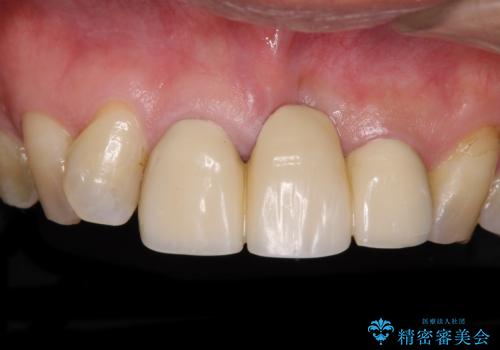

変色した前歯 オーダーメイドタイプのオールセラミッククラウン

変色した前歯のオールセラミック治療